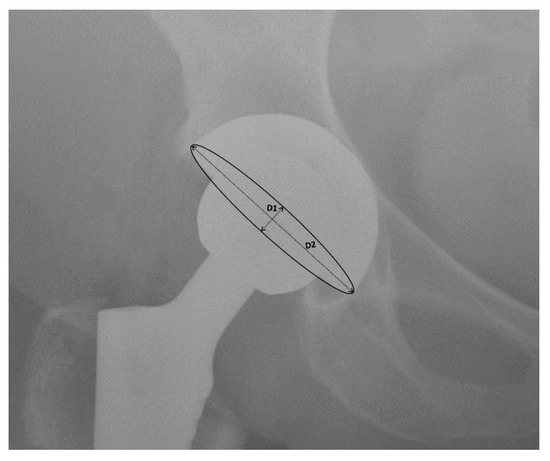

3.4. Mean Radiographic Cup Anteversion

3.5. Leg Length